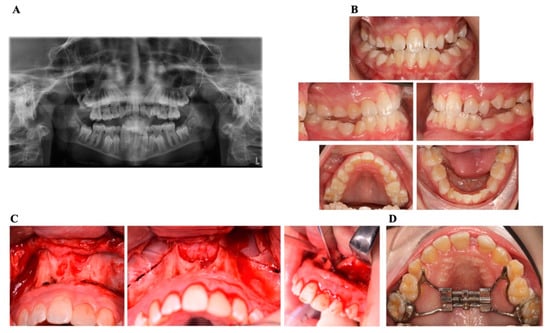

| 1 | 11 years | Piriform aperture stenosis, nasal stenosis, single central incisor | Nasal obstruction, failed orthodontic expansion, skeletal discrepancy | Quad-Helix expansion (unsuccessful) | Planned SARPE with paramedian osteotomy | Follow-ups |

| 2 | Patient history spans from birth to 11 years old | Upper airway obstruction, adrenal insufficiency, progressive hearing loss | Cyanosis at birth, respiratory distress, sleep-related breathing difficulties | Neonatal surgery (incomplete correction), hearing aid placement | Conservative management, ENT and audiology follow-up; Late intervention: planned surgical airway expansion | Underwent SARPE at age 11; current follow-ups at age 14 |

| 3 | 3 years | Piriform aperture stenosis, single primary central incisor | Snoring, noisy breathing, recurrent respiratory infections | Nasal wall drilling for airway relief | Neonatal palatal expander planned | Possible future surgical correction if nasal obstruction worsens |

| 4 | 20 days | Pyriform aperture stenosis, postoperative complications with nasal synechiae | Respiratory distress, feeding difficulty, desaturation episodes | Sub-labial PAS correction, nasal cannula placement | Scheduled for additional surgery to release nasal adhesions | Potential additional interventions depending on airway development |